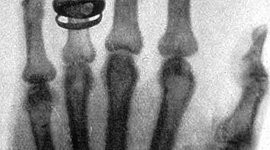

Concepción de salud a lo largo de la historia